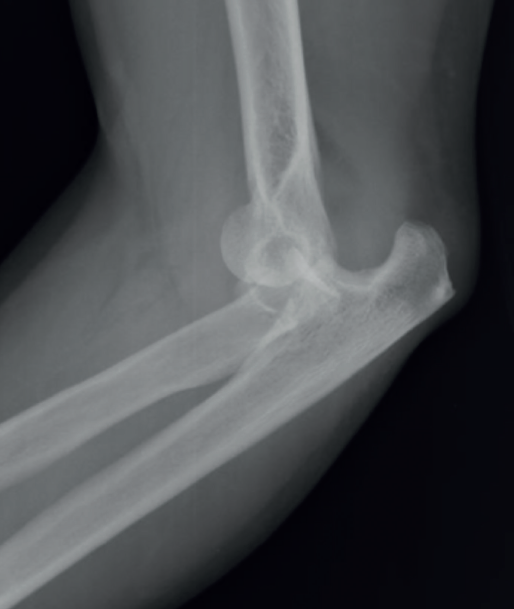

El primer patrón de inestabilidad se conoce como tríada terrible del codo. Se produce tras una caída con el brazo en extensión, con supinación, valgo y carga axial, y la fuerza progresa desde estructuras laterales a mediales. En primer lugar, se produce una disrupción del LCL ulnar (LCLU), que se arranca del epicóndilo lateral; a continuación, tiene lugar una luxación inferior de la cabeza radial; y, finalmente, las fuerzas de cizallamiento pasan a través de la punta de la coronoides hasta lesionar el LCM. Esto ocasiona una inestabilidad en valgo posterolateral rotatoria.

Este tipo de lesiones se puede confundir con una fractura-luxación de Monteggia-Bado I. La diferencia es que no se ve afectada la articulación radiocubital proximal y los ligamentos colaterales medial y lateral permanecen anclados al fragmento distal del cúbito (Figuras 1, 2 y 3).